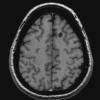

VASCULAR

Cavernous Angioma (13)